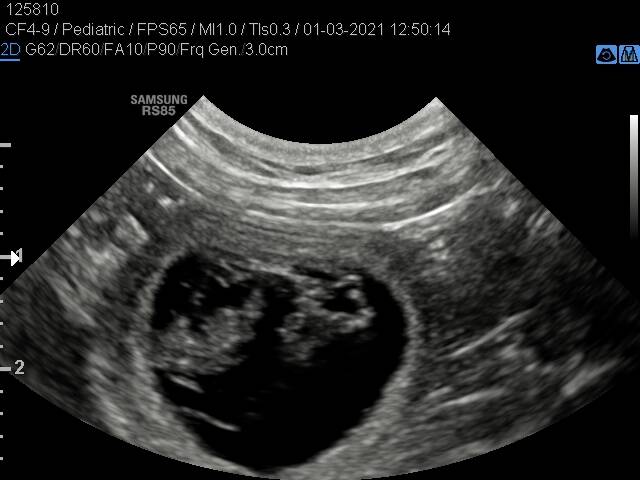

De echo's van 01/03/2021.

Deze echo's zijn gemaakt op 1 maart 2021.

Het moment dat we er achter kwamen dat Noesja 4 weken drachtig is.

Op deze echo foto's waren de puppy's 1,5 cm.